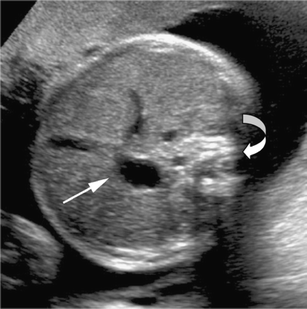

We report a case of intestinal malrotation without any associated GI tract complications diagnosed antenatally by fetal MRI. Antenatal US revealed a midline stomach. Subsequent fetal MRI confirmed the midline stomach and, in addition, revealed all loops of small bowel to the right of the midline and all large bowel to the left. All these features were consistent with intestinal malrotation. There was no abnormal bowel wall thickening, bowel dilatation, ascites or polyhydramnios. To our knowledge, this is a unique case of intestinal malrotation without associated GI tract complications diagnosed antenatally on fetal MRI.

Fig. 1